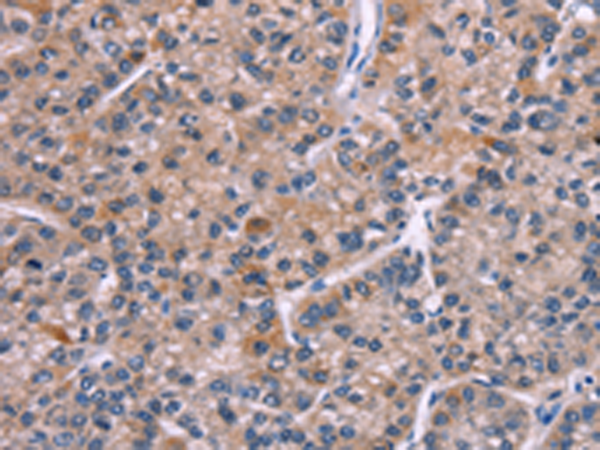

分类: 科研抗体货号: P07998别名: M6A; GPM6应用: WB,IHC反应种属: Human, Mouse, Rat